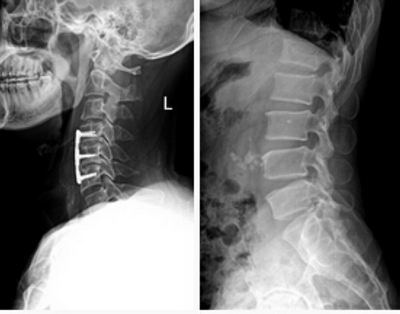

★適用于全身各部位攝影,包括常規(guī)攝影(立位攝影、臥位攝影等,如胸片、頸椎、腰椎、腹部、頭顱、四肢等)和特殊攝影(傾斜攝影、角度攝影等,如瓦氏位、骶髂關(guān)節(jié)、髕骨軸位、跟骨軸位等)。